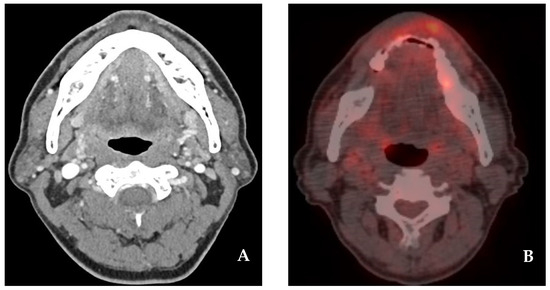

2.2. Case 2